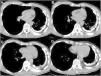

Pleural calcification mimicking a rib

Calcificación pleural similar a una costilla